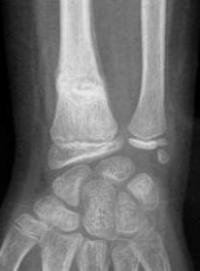

Fracture métaphysaire distale du radius : radio de Face initiale

Aspect de fracture en motte de beurre